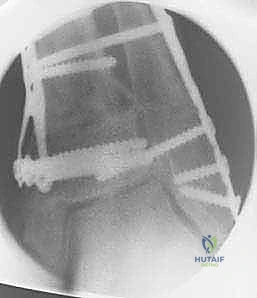

5. التثبيت الصلب وزراعة الطعم العظمي

في حالة "فتح الإسفين"، يتم وضع طعم عظمي (يؤخذ غالباً من عظم الحوض للمريض أو طعم صناعي متقدم) لملء الفراغ. بعد ذلك، يقوم الدكتور هطيف بتثبيت العظم في وضعه الجديد القويم باستخدام شرائح معدنية تشريحية مصممة خصيصاً لهذه المنطقة (Anatomical Locking Plates) ومسامير قوية. هذا التثبيت الصلب يضمن التئام العظم بشكل صحيح.

- الأشعة السينية للمتابعة: في الأسبوع السادس، يقوم الدكتور هطيف بإجراء أشعة سينية للتأكد من بدء التئام العظم.